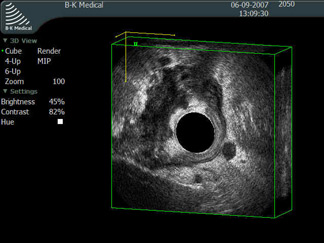

Эндоректальное 3D ультразвуковое исследование - местнораспростаренная опухоль прямой кишки.